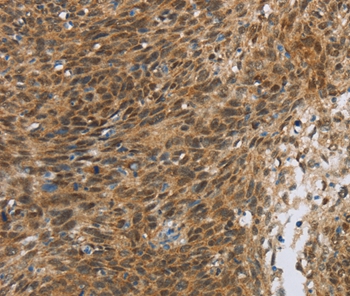

Immunohistochemical analysis of paraffin-embedded Human cervical cancer tissue using #36861 at dilution 1/30.

Immunohistochemical analysis of paraffin-embedded Human thyroid cancer tissue using #36861 at dilution 1/30.